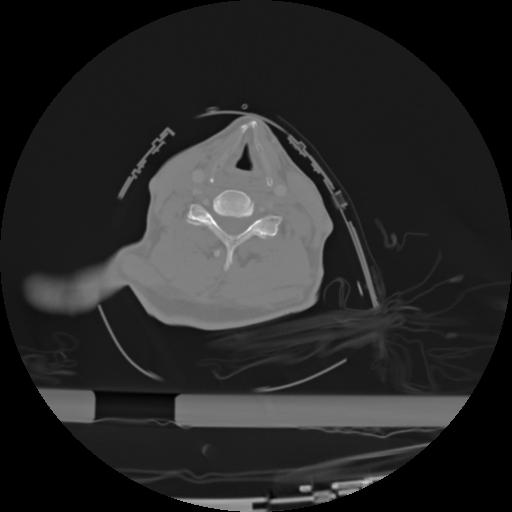

21 ANGIO,CE,Axial,3.0,ANGIO,,